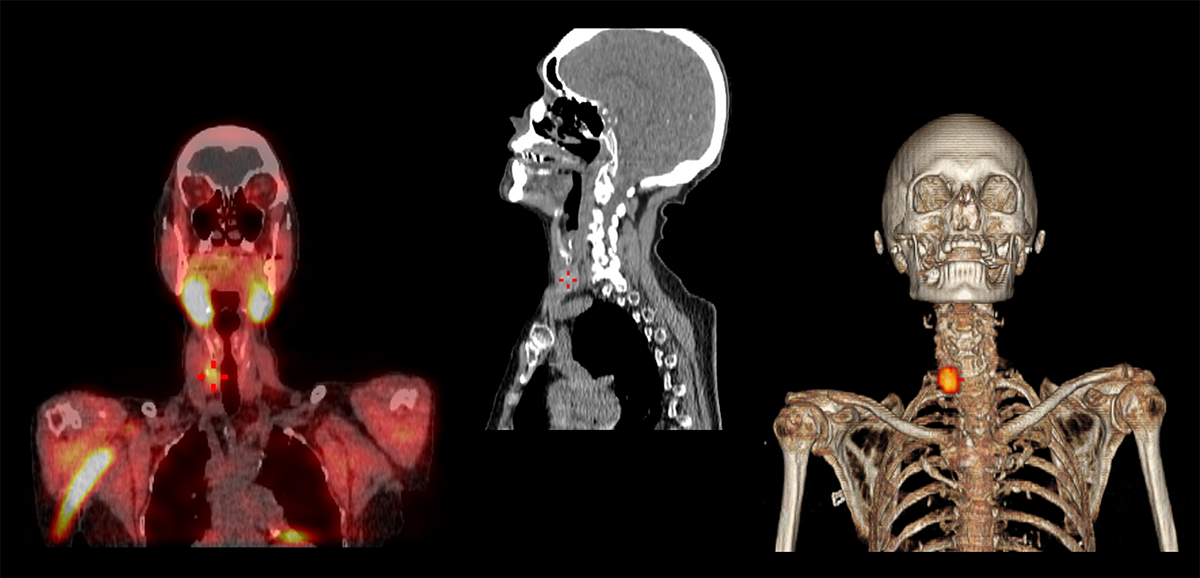

First and foremost, Declerck says patients come first. “The most important people in my department are my patients. They have rights and expectations, and they deserve to get the best in patient-centered care. It’s important to meet with patients and explain what you are going to do and what you’re expecting to see from imaging tests. Our powerful modalities give us the opportunity to scan the whole body and see the entirety of our patient and not only the sick organ.”

Designing a workplace infrastructure to support the complex operational requirements and technology needs for an efficient nuclear medicine department is key, says Declerck. As his facility expanded its investment in molecular imaging with a new positron emission tomography/computed tomography (PET/CT) scanner and digital single-photon emission computerized tomography/computed tomography (SPECT/CT) scanner, Declerck took the opportunity to optimize the layout of the department.

In contemporary nuclear medicine, the use of more complex and equally individualized molecular imaging can be critical in optimizing care. Putting tracers into daily clinical practice requires knowledge from specialists who are up to date on the latest techniques. It is also imperative to implement an efficient, standardized workflow to support them, which allows the department to maintain quality control measures and accreditation.